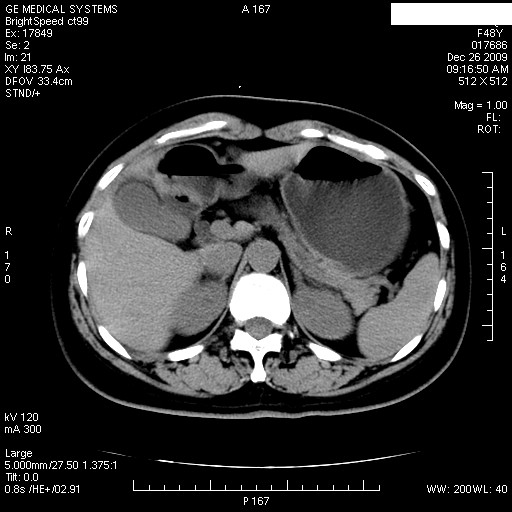

经过抗炎解痉镇痛治疗一周后复查ct如下:

1.图像看上去不是同一人(前组图像十二指肠未见明显异常,后组图像可见十二指肠占位)

2.后组图象印像

a.十二指肠球部前壁占位

b.坏蛆性胆囊炎,胆囊-结肠瘘(瘘口微小且时间较短,结肠内容返流入胆囊,形成胆囊壁钙化,胆囊内钙盐等沉积)

c.胆管炎,肝外胆管轻度扩张

坏蛆性胆囊炎,胆囊-结肠瘘,胆囊内钙盐等沉积.

1)肝内外胆管扩张,原因待查。2)胆囊内药物沉积?